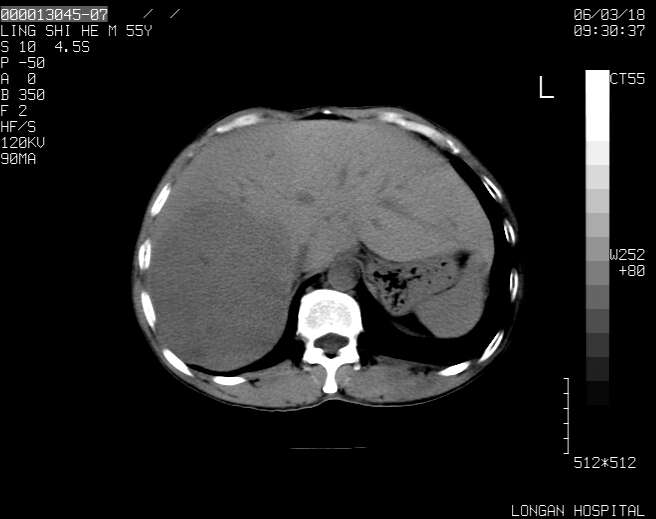

以下是引用guzhongliangddd在2006-3-21 22:13:00的发言:[br]病灶主要位于肝右叶的后份,内见异常血管,门脉主干及右支受侵{提示有癌栓形成},门腔间隙内见增大淋巴结。肝左叶内未见异常。

以下是引用zhuxinli在2006-3-22 1:23:00的发言:[br][br] 病灶主要位于肝右叶的后份,内见异常血管 .门脉右支截断,右叶前段早期强化(考虑动静脉漏),腹膜后肿大淋巴结,病灶逐渐强化,考虑为胆管细胞癌[br]